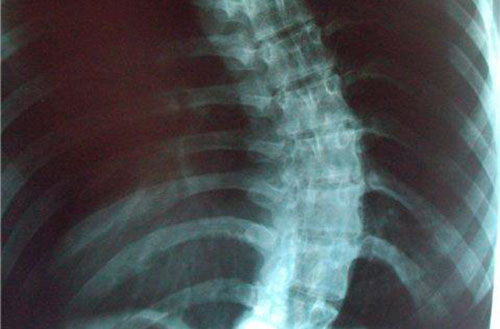

Любой вид деформации позвоночного столба во фронтальной поверхности, искривления его вправо, или влево, несвойственные физиологическим изгибам позвоночного столба, носят название сколиоза и являются бесспорной патологией. Позвоночный сколиоз – опасное отклонение от нормы.

Сколиоз – изгиб, который не предусмотрен ни целесообразностью, ни природной компенсаторной функцией и в любой степени своего прогрессирования признается патологическим процессом.